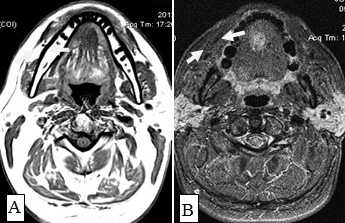

С помощью КТ сложно было выявлять опухоли малых размеров (Т1стадия) и их границы в результате низкой контрастности, а также новообразования с поверхностным распространением (рис. 1). Вместе с тем, 72,0% обследованных больных имели Т3, Т4 стадии опухолевого процесса и после болюсного введения контрастного вещества контрастность опухоли повышалась. С увеличением размера опухоли отмечалась неоднородность усиления из-за наличия некроза (рис. 2). Жировые пространства подъязычной области в нормальном состоянии представляют собой симметричную зону низкой плотности между челюстно-подъязычной и подбородочно-подъязычной мышцами. Облитерация жировых пространств подъязычной области служила основным показателем опухолевого поражения при выявлении небольших образований дна полости рта (рис. 3,4).

Рис.1. Пациент Ж., 58 лет. МСКТ ротоглотки в аксиальной проекции: А - нативное исследование, В - с внутривенным болюсным контрастированием. Небольшая инфильтративная опухоль ротоглотки (левой небной миндалины Т1 стадии). Границы опухоли не дифференцируются, накопление контраста слабое (показатели плотности в нативной фазе исследования 45 ед.Н, после внутривенного болюсного усиления - 56 ед.Н). Определяется смещение левой стенки ротоглотки, сглаженность контура (стрелки)

Рис. 10. А. Пациент Е., 52 года. МРТ полости рта, ротоглотки в аксиальной проекции, Т1-ВИ. Опухоль языка небольших размеров, границы визуализируются с трудом за счет перифокального отека (стрелки); В. Тот же пациент. МРТ в аксиальной проекции, Т2 с подавлением сигнала от жировой ткани. Визуализируются границы опухолевого узла, размеры опухоли языка четко определяются (стрелки)